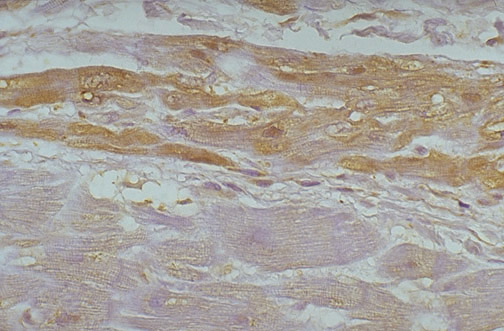

| The cardiac conduction system is difficult to see histologically in humans, consisting of specialized myocardial fibers that conduct electrical impulses more readily than surrounding myocardial fibers. The more neural features of these fibers is brought out by this S100 immunohistochemical stain, which highlights the AV node above in cross section. Below, at high magnification darker red brown color of the smaller, more irregular specialized conduction fibers is apparent, compared to the adjacent myocardial fibers. |